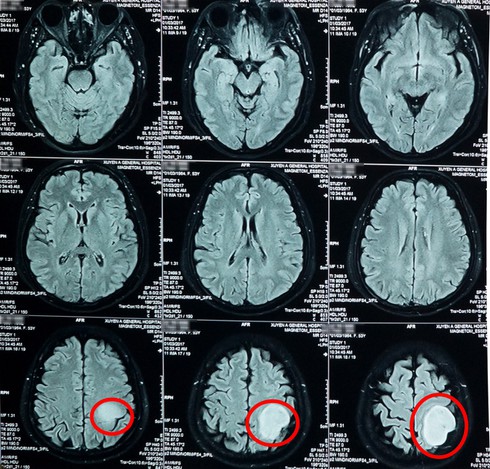

Qua kết quả chụp MRI, các bác sĩ xác định bệnh nhân có khối u lớn trong não trái, đường kính khối u khoảng 5cm, to bằng một trái banh tennis. Bệnh nhân và người nhà được tư vấn kỹ lưỡng để chuẩn bị phẫu thuật.

Hình ảnh khối u qua phim chụp |